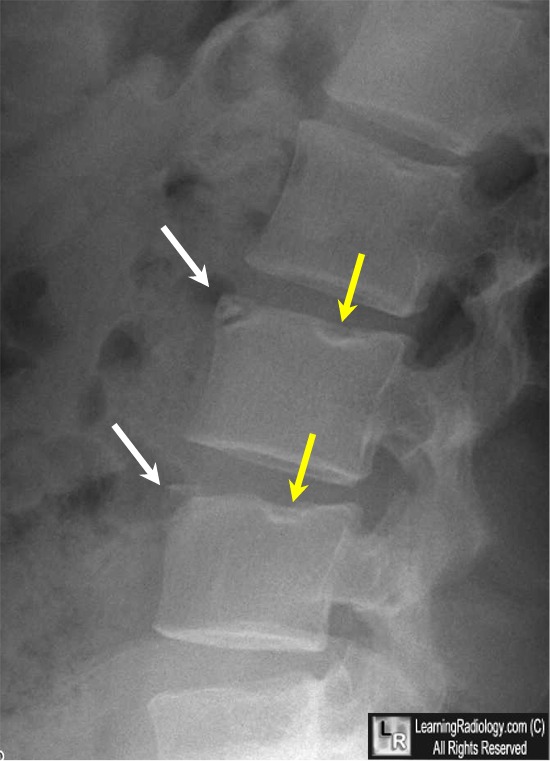

From www.learningradiology.com

LearningRadiology What Is Schmorl's Nodes Lumbar Spine A schmorl’s node, also known as an intervertebral disc herniation, is the protrusion of the cartilage of a. Schmorl nodes, also known as intravertebral disc herniations, refer to protrusions of the cartilage of the intervertebral disc through the vertebral body. What is a schmorl’s node? Schmorl's nodes are disc herniations into the spinal bone, usually in the thoracic or lumbar. What Is Schmorl's Nodes Lumbar Spine.

Lateral lumbar spine projection demonstrating the Schmorl node at L2 What Is Schmorl's Nodes Lumbar Spine Schmorl nodes, also known as intravertebral disc herniations, refer to protrusions of the cartilage of the intervertebral disc through the vertebral body. They can be painful, cause inflammation, and lead to disc degeneration or infection. Schmorl’s nodes are a common spinal disc herniation in which the soft tissue of the intervertebral disc bulges out into the adjacent vertebrae through an. What Is Schmorl's Nodes Lumbar Spine.